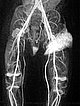

Contrast-enhanced dynamic MR angiography (coronal plane).

30 s after contrast injection in the early arterial phase, there is immediate early enhancement of the tumor in the left groin.

Contrast-enhanced dynamic MR angiography (coronal slice orientation).

41 s after contrast injection in the late arterial phase, there is further, rather diffuse, strong enhancement of the tumor ("tumor-blush") in the left groin, corresponding to a solid vascular tumor.

57 s after contrast injection in the early venous phase, the entire tumor continues to enhance strongly. The image now also displays a dilated early drainage vein in comparison of sides. The venous drainage (left iliac vein) has dilated because of the strong tumor perfusion with increased venous outflow.

130 s after contrast injection in the late phase, the strong enhancement of the tumor in the left groin remains, no early "wash-out". Additionally, the enhanced venous drainage via the left iliac veins still contrasts.